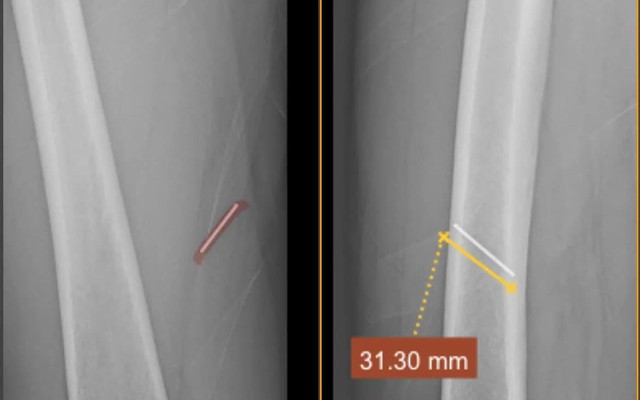

Một bệnh nhân bị tai nạn lao động, dị vật kim loại nằm sâu trong tổ chức phần mềm đùi đã được các bác sĩ Trung tâm Y tế Quế Võ (Bắc Ninh) xử trí kịp thời, đảm bảo an toàn.

Bệnh nhân nam, 63 tuổi, làm nghề thợ mộc. Trong quá trình lao động, bệnh nhân không may bị súng bắn đinh bắn một chiếc đinh kim loại vào mặt trong đùi. Dị vật nằm sâu trong tổ chức mỡ và cơ, tiềm ẩn nguy cơ tổn thương mô mềm, nhiễm trùng và biến chứng nếu không được xử trí đúng cách.

Ngay sau khi tiếp nhận, các bác sĩ đã khai thác bệnh sử, thăm khám lâm sàng và chỉ định các phương tiện chẩn đoán hình ảnh nhằm xác định chính xác vị trí, độ sâu và hướng đi của dị vật. Trên cơ sở đó, ekip Khoa Ngoại tiến hành thủ thuật lấy dị vật với sự hỗ trợ của trang thiết bị chuyên môn.